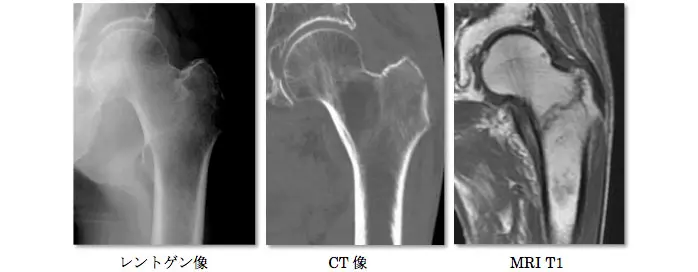

著しい疼痛があるもレントゲンで異常を認めない場合は、骨挫傷や不全骨折(亀裂骨折、若木骨折、竹節骨折)、疲労骨折などの不顕性骨折を認めることがある。不顕性骨折は骨梁の連続性は絶たれているが、骨膜の連続性は保たれているため、レントゲンやCTで異常所見を認めないことが多く,MRI T1強調像で低輝度を呈することによって診断される。外傷後や高齢者でレントゲン上明らかな骨折がないにも関わらず疼痛が持続する場合には、不顕性骨折を疑い、数日後、受傷1週間後のレントゲン再検査や、適宜CTやMRIを施行することが必要である。不全骨折はCTで骨折が判明することもあるが、骨挫傷に関してはCTで有意な所見を認めないことが多く、MRIが最も有用である。また、レントゲンでは骨梁の修復反応により、継時的に骨硬化像を認めるようになる。 全症例にMRIを施行することは困難なことがあり、高齢者の転倒を診る時にはレントゲンでは検出されない骨折があることを念頭に置き、患者にもその旨を説明の上、適宜、レントゲン再検査することが重要である。

左大腿骨頸部骨挫傷の他症例

CT像で転子部に骨折線とMRI T1強調像で同部位に低輝度を示す骨折線を認める